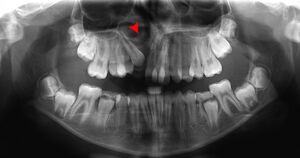

The density of the alveolar bone in a given area also determines the route that dental infection takes with abscess formation, as well as the efficacy of local infiltration during the use of local anesthesia. In addition, the differences in alveolar process density determine the easiest and most convenient areas of bony fracture to be used, if needed during tooth extraction of impacted teeth. During chronic periodontal disease that has affected the periodontium (periodontitis), localized bone tissue is also lost. The radiographic integrity of the lamina dura is important in detecting pathologic lesions. It appears uniformly radiopaque (or lighter).[24]

Alveolar bone grafting in the mixed dentition is an essential part of the reconstructive journey for cleft lip and cleft palate patients. The reconstruction of the alveolar cleft can provide both aesthetic and practical advantages to the patient.[25] Alveolar bone grafting can also bring about the following benefits: stabilisation of the maxillary arch; aid of eruption of the canine and sometimes lateral incisor eruption; offering bony support to the teeth lying next to the cleft; elevate the alar base of the nose; aid sealing of oro-nasal fistula; permit insertion of a titanium fixture in the grafted region and achieve good periodontal conditions within and next to the cleft.[26] The timing of the alveolar bone grafting takes into consideration both eruption of the canine and lateral incisor. The optimal time for bone grafting surgery is when a thin shell of bone still covers the soon erupting lateral incisor or canine tooth close to the cleft.[26]